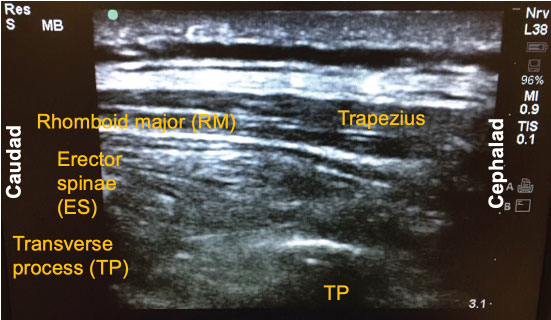

Since its introduction a few years ago, there have been numerous descriptions published on how to perform the ESP block. The following is a brief summary of the technique used to perform the block on our previously-described patient. With the patient in the sitting position, a high-frequency linear ultrasound probe was placed longitudinally on the patient's back approximately 3 cm lateral to the 5th thoracic (T5) spinous process. Three muscles above the hyperechoic transverse process were identified: trapezius, rhomboid major, and erector spinae in order of superficial to deep layers (Figure 1). A 10-cm 18-gauge Tuohy needle was inserted in-plane with the ultrasound beam at a 30° angle in a cephalad to caudal fashion. The tip of the needle was directed to the myofascial plane between the erector spinae muscle and the T5 transverse process (Figure 2). Following negative aspiration of blood, 20 mL of 0.25% ropivacaine was incrementally injected. Linear fluid spread deep to the erector spinae muscle was visualized in real-time. Finally, for continuous postoperative infusion, a 20-gauge catheter was threaded through the Tuohy needle and secured at the skin with a goal of having 5 cm of catheter left in the myofascial plane.

Figure 1: Three muscle layers for the erector spinae plane (ESP) block: Trapezius, rhomboid major (RM), and erector spinae (ES).